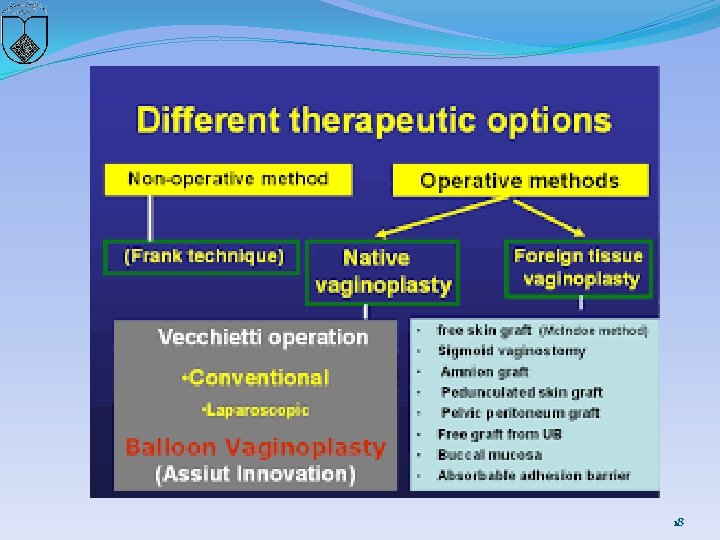

�first line for therapy : Nonsurgical treatment with selfdilatation �Surgery: if nonsurgical therapy fails or, if after extensive counseling, a patient elects a surgical approach �Mc. Indoe procedure �Williams vaginoplasty �Sigmoid vaginoplasty �Vecchietti procedure �Davydov procedure 17

18